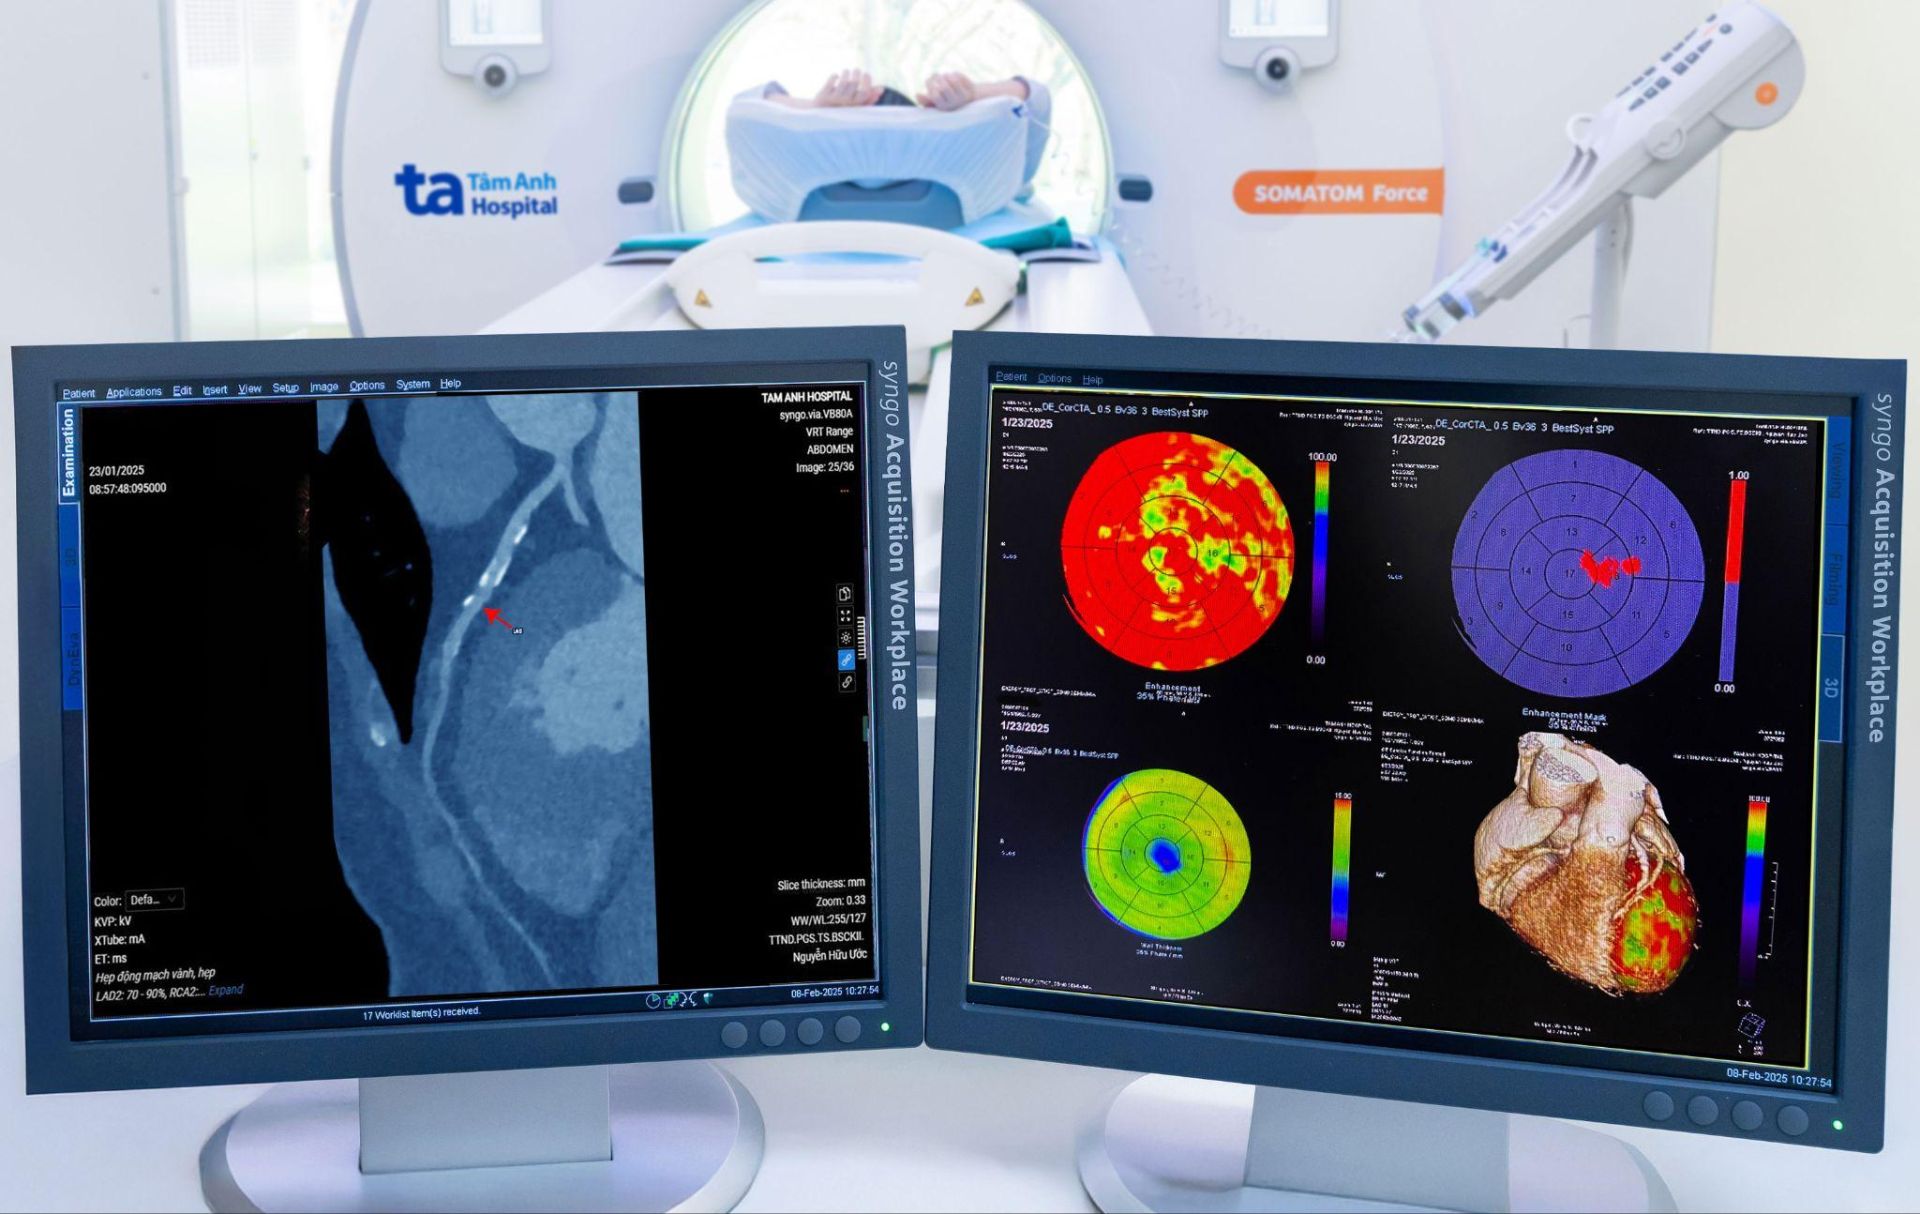

Như trường hợp bà Vũ Thị Hồng, 63 tuổi, Hà Nội, nhịp tim thường xuyên trên 100 lần/phút, nhịp không đều. Nhiều lần đi khám sức khỏe, bà muốn chụp CT tầm soát mạch vành nhưng không thể thực hiện do nhịp tim cao, gây nhòe mờ phim chụp. Đến BVĐK Tâm Anh Hà Nội, bà Hồng được bác sĩ chỉ định chụp mạch vành và tầm soát toàn thân bằng máy CT Somatom Force VB30. Kết quả cho thấy bà bị hẹp mạch vành tới 90% kèm rối loạn tưới máu. Người bệnh được chỉ định lập tức đặt stent nong mạch vành, vượt qua nguy kịch, hiện sức khỏe ổn định.

Kết quả chẩn đoán hình ảnh tối ưu như trường hợp bà Hồng chính là nhờ siêu máy chụp CT có trường chụp lên đến 80 cm, gấp 5 lần CT thông thường. Máy có thể chụp toàn cơ thể hoặc các vùng cơ thể lớn chỉ trong một lần quét, giảm thời gian chụp và hạn chế việc bệnh nhân phải thay đổi tư thế. Máy có khả năng chụp cực nhanh, đóng băng chuyển động của mạch vành trong 1 nhịp tim, tạo ra hình ảnh mạch vành rõ nét, đồng thời tự động lập biểu đồ đánh giá vùng tưới máu của cơ tim.

CT Somatom Force VB30 là máy đầu tiên và duy nhất có khả năng chụp cùng lúc mạch vành và tưới máu não; chụp mạch vành, mạch não, mạch chủ ngay trong một lần. Đây cũng là máy chụp CT động học 4D tốt nhất hiện nay, với khả năng ghi lại diễn biến dòng máu theo thời gian thực, giúp bác sĩ lên kế hoạch điều trị bệnh mạch máu chính xác. Ưu điểm vượt trội này đặc biệt hữu hiệu với các trường hợp bệnh lý hiếm gặp hoặc dấu hiệu bệnh không đặc trưng.